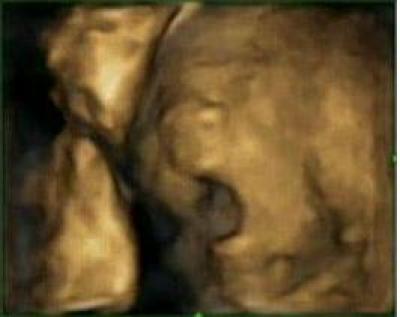

Ultrasound pictures show difference in fetus yawning and other mouth openings

Ultrasound scans of faces in utero can distinguish between when a fetus yawns and when it just opens its mouth, according to research published November 28 in the open access journal PLOS ONE by Nadja Reissland from the University of Durham and colleagues at other institutions.

The researchers found that during the period between 24 to 36 weeks of gestation, they could distinguish between yawns and simple mouth openings on ultrasound images of fetal faces. They report that simple mouth openings occur less often than yawns and the frequency of these openings declines from 24 weeks of gestation onward. More than half of all mouth openings are yawns at 24 weeks of gestation, and the frequency of yawns begins to decline at a later stage (28 weeks onward).

The study suggests that trends in yawning behavior may potentially be used to track healthy fetal development. Reissland says, "Fetus yawning is not contagious, nor do they yawn because they are "sleepy". Instead, frequency of yawning in the womb might be related to activity-dependent brain maturation early in gestation."